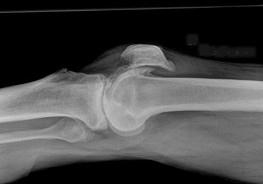

问题 男,76岁,左膝关节长久站立时疼痛,可扪及捏发音,请结合图像,选出最可能的诊断 ( )

选项 A、创伤性关节炎 B、肥大性骨关节病 C、畸形性骨炎 D、神经性关节病 E、退行性骨关节病

答案 E